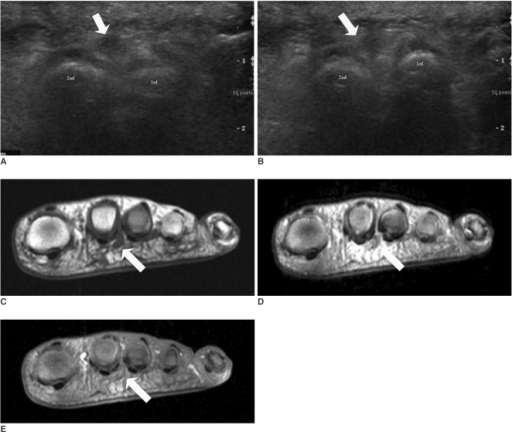

Clinical image for Morton's Neuroma

What investigations would you order? Describe the imaging findings and their interpretation.